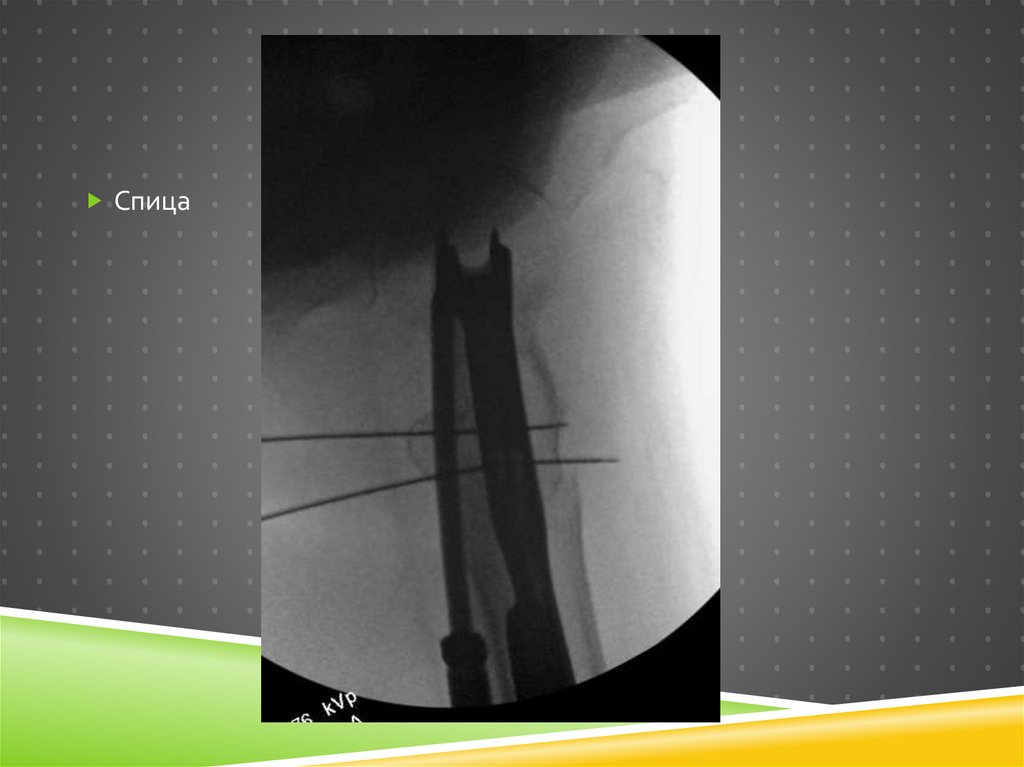

31. Poller (transmedullary) спицы

POLLER (TRANSMEDULLARY) СПИЦЫ

31